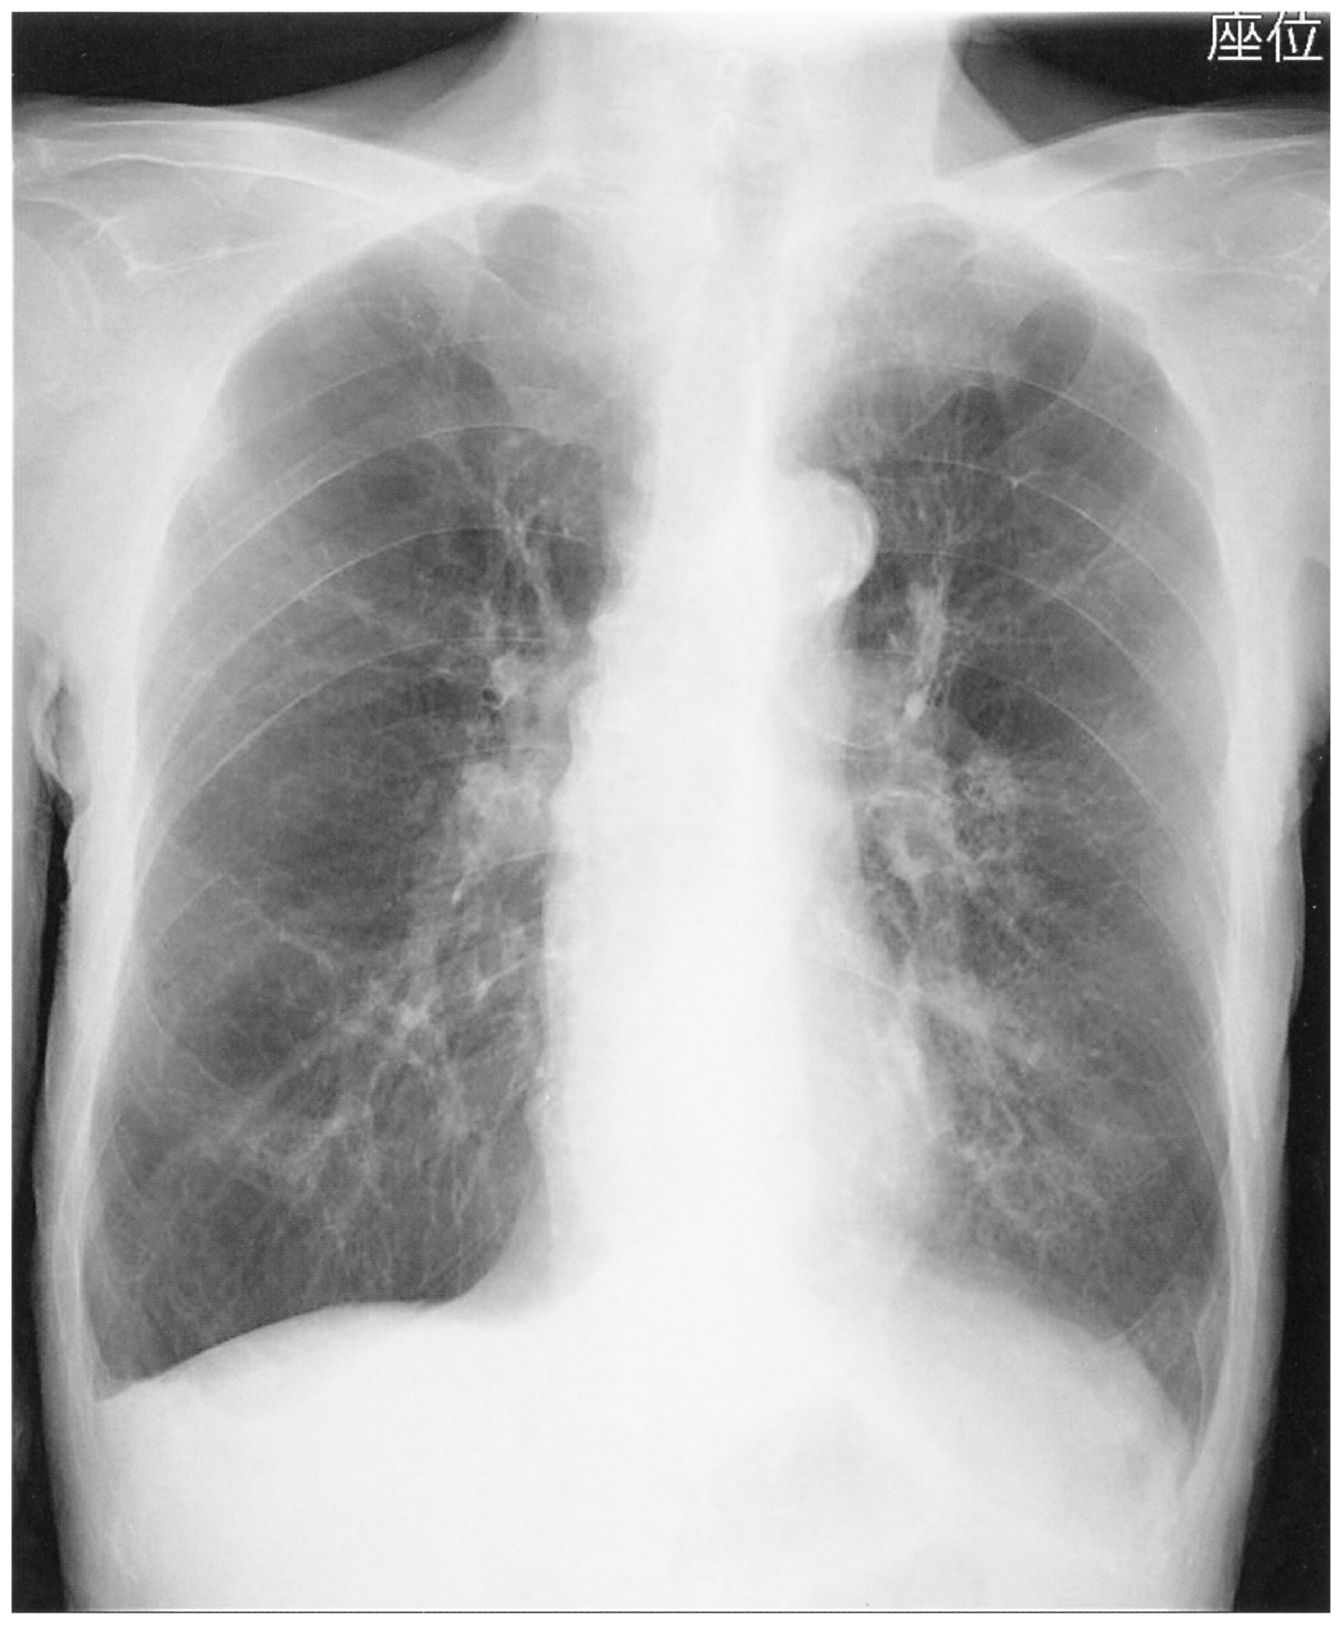

血液所見:赤血球436万,Hb 13.0g/dL,Ht 39%,白血球16,460(好中球89%,好酸球0%,好塩基球0%,単球6%,リンパ球5%),血小板33万,PT-INR 1.0(基準0.9~1.1),Dダイマー0.5μg/mL(基準1.0以下)。血液生化学所見:総蛋白5.7g/dL,アルブミン3.3g/dL,総ビリルビン2.1mg/dL,直接ビリルビン0.6mg/dL,AST 27U/L,ALT 16U/L,LD 219U/L(基準124~222),ALP 112U/L(基準38~113),γ-GT 22U/L(基準13~64),CK 39U/L(基準59~248),尿素窒素28mg/dL,クレアチニン0.6mg/dL,尿酸6.9mg/dL,血糖177mg/dL,HbA1c 5.6%(基準4.9~6.0),Na 138mEq/L,K 3.7mEq/L,Cl 100mEq/L。CRP 10.1mg/dL。動脈血ガス分析(room air):pH 7.45,PaCO2 38 Torr,PaO2 54 Torr,HCO3 24mEq/L。心電図は洞性頻脈でST-T変化を認めない。胸部エックス線写真を下に示す。

無料会員登録していただくと、実際の解説をすべて見ることができます。急性の呼吸困難を主訴とする疾患としては,喉頭浮腫,気道異物,自然気胸,気管支喘息,慢性閉塞性肺疾患の急性増悪などの呼吸器疾患,心不全(急性,慢性の急性増悪),肺血栓塞栓症などの循環器疾患が代表的である。この症例では呼吸器感染症と心不全が疑われるが,胸部エックス線写真は肺炎像というよりも両心不全を示唆する所見を示している。診断:心不全(両心不全)(Nohria分類wet and warm) 選択肢考察 ×a 強い呼吸困難,胸痛などにより安静が保てない場合には,血管拡張による前負荷軽減と,交感神経抑制による心筋酸素消費量の減少を目的としてモルヒネを使用する。この症例ではモルヒネが必要となるほどの興奮状態ではない。